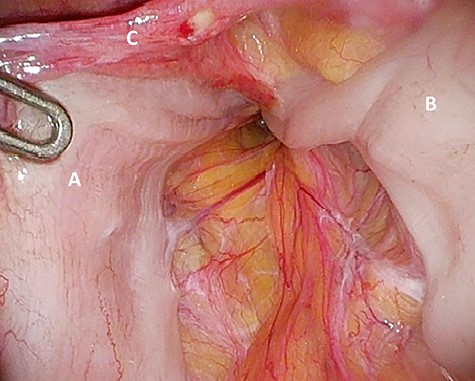

Considering the patients’ comorbidities (obesity, Type 2 diabetes mellitus), a re-TAPP was performed to avoid possible wound complications. The recurrent hernia was presumably confirmed as a lateral inguinal hernia. After dissecting dense fibrotic scar tissue around the previous mesh preperitoneally, the hernia sac was released. A large spermatic cord lipoma was found and dissected (Figs 1 and 2). A new mesh (BARD® 3D Light Mesh, 10 × 15 cm) was inserted.

Suspected indirect inguinal recurrence hernia with a large spermatic cord lipoma (A), epigastric vessels (B), ductus deferens (C), peritoneum with previous mesh (D).